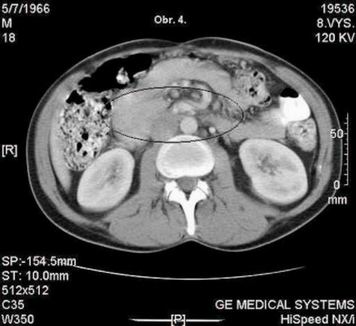

Pacient absolvuje CT vyšetření, kde je popsána velmi suspektní metastáza vpravo subpleurálně, na rozhraní S 9/10 - obr. 1., dále v retroperitoneu paket patologických uzlin 27 x 23mm - mezi aortou a dorzální plochou pankreatu, v úrovni dolního okraje pankreatu. obr. - 2., 3., 4. CT plic zobrazilo v mediastinu jen několik drobných uzlin nad bifurkací, velikosti do 9 mm. Nejsou vzhledu charakteristického pro patologické uzliny. V plicním parenchymu vpravo v S 10 subpleurálně metastatické ložisko velikosti 2O mm, polokulovité zesílení pleury kraniálně v S 1O vpravo - obr. 1. a suspektní drobné subpleurální ložisko velikosti cca 5 mm vpravo v S 2. Vlevo bez ložiskových změn, bez fluidothoraxu. Hodnoty tumormarkerů nepřesahují referenční meze - CEA 2.7 ug/l (referenční hodnota do 4.6), CA 19-9 < 2 kU/l (referenční hodnota do 37.0).